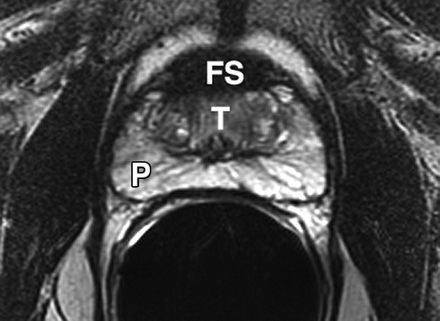

Although most prostate cancers originate in the PZ, up to 24% may arise in the transition zone (TZ) [5] and would therefore be missed by any biopsy protocol that sampled only the PZ.

Isolated TZ tumours are thought to have a favourable prognosis, being of low Gleason grade, infrequently associated with prostatic intraepithelial neoplasia (PIN) [9] and often discovered incidentally at transurethral resection of the prostate (TURP).

- Some have advocated routine TZ biopsies for all men presenting with a raised PSA level but a normal DRE [10].

Sextant biopsies were taken routinely ≈ 1 cm apart in the parasaggital plane bilaterally, at the base, mid-gland and apical regions of the prostate, as described by Hodge et al. [1]. In addition, six further biopsies were obtained, two from the TZ and four from the lateral PZ, as depicted in Fig. 1. The TZ biopsies were taken at the level of the mid-gland where the TZ was most prominent. The lateral PZ biopsies were taken by positioning the probe just medial to the lateral edge of the prostate at the base and mid-gland regions bilaterally, as described by Chang et al. [8]. This method generally allowed any area of DRE abnormality or suspicious hypoechoic lesion noted on TRUS to be incorporated into the biopsy protocol. All patients underwent the same biopsy strategy with no variance for gland size. Biopsies were obtained using an 18 G core-biopsy needle mounted on a spring-loaded automatic biopsy gun. All patients were placed in the left lateral decubitus ('knee-chest') position and all were examined with no prior bowel preparation. The procedure was generally well tolerated and no patient required intravenous sedation or narcotic analgesia. All TRUS was undertaken by the same operators (D.R.G. and N.S.), either personally, or when supervising a higher urological trainee.